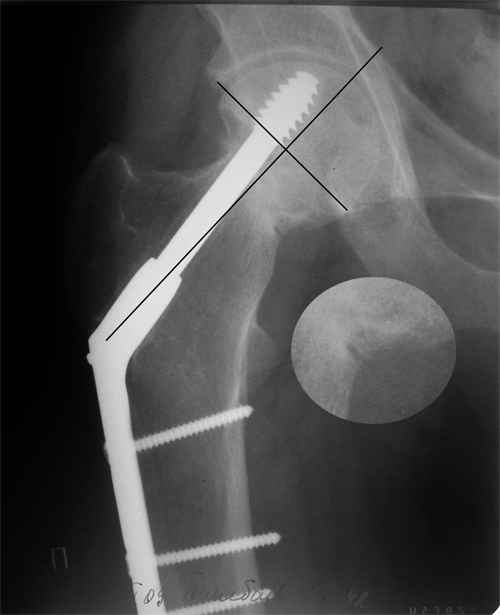

Больной Т. 1966 г.р.Травма 28.06.2007. Прооперирован в г. Бишкек, Оп: Остеосинтез правого бедра системой DHS. В последующем беспокоили периодические боли в правом тазобедренном суставе с иррадиацией в коленный сустав в область передней поверхности правого бедра. Лечился амбулаторно с незначительным эффектом. В 07.04.2008 по 08.05.2008 года лечился в госпитале ГУВД и СО в стационаре с Срастающийся перелом шейки правого бедра в условиях фиксации системой DHS – боли уменьшились.Боли обострились 03.02.2009 внезапно, госпитализирован. Результат - Псевдоартроз шейки правого бедра (имеются косвенные признаки разрушения спонгиозной части головки бедра)Планируется - Работает милиционером. Имеющийся опыт протезирования у данной категории во всех случаях в ближайшее время заканчивался дисквалификацией. Работоспособный возраст (43 года).Наиболее приемлемым и реальным методом лечения предполагается: Удаление конструкций из бедра. Заполнение полости от винта монолитным аутотрансплантатом из крыла (крылев) подвздошной кости. Медиализация большого вертела. Предполагаемый период нетрудоспособности 3-4 мес.

На более раннем снимке репозиция была, мягко говоря, далека от идеальной. Плюс перелом шейки слишком проксимальный для фиксации одном винтом. Неудача тут закономерный исход.

Но в данном случае DHS сыграл как имплант с угловой стабильностью, что привело к прорезыванию импланта в верхнем сегменте головки. Отсутствие трехточечной опоры и длинный имплант увеличивают нестабильность в шейке.

Если на рентгенограмме произошли изменения положения импланта более чем на 5 градусов от первоначального, миграция шурупов более чем 15 мм от кортекса, также потеря репозиции на 10 мм - это свидетельство несостоятельности импланта. Компьютерная томография уточнит все сомнения. В таких случаях бесполезно ожидать, что перелом срастется, лучше своевременно сообщить больному и принимать решительные меры по реконструкции.